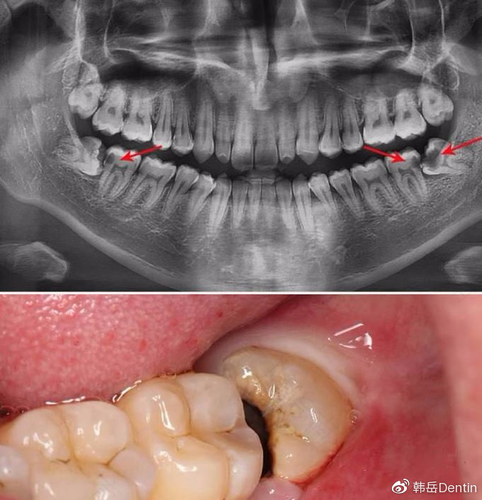

当长有尽头牙的时候,为了防止对身体造成困扰,建议将牙齿拔除,因为它后续可能会出现感染,引起疼痛,导致身体不适。有些患者是没有必要拔除的,需要根据患者的情况来决定,建议先让牙医给检查一下,然后决定该怎么做。

拔除尽头牙一定要让专业的牙医给拔,手术会有一定的危险,专业医生拔牙可以降低危险,如果患者有糖尿病、心脏病,那么拔除的时候还可能引起并发症,所以手术之前要慎重,根据身体情况决定治疗方式。